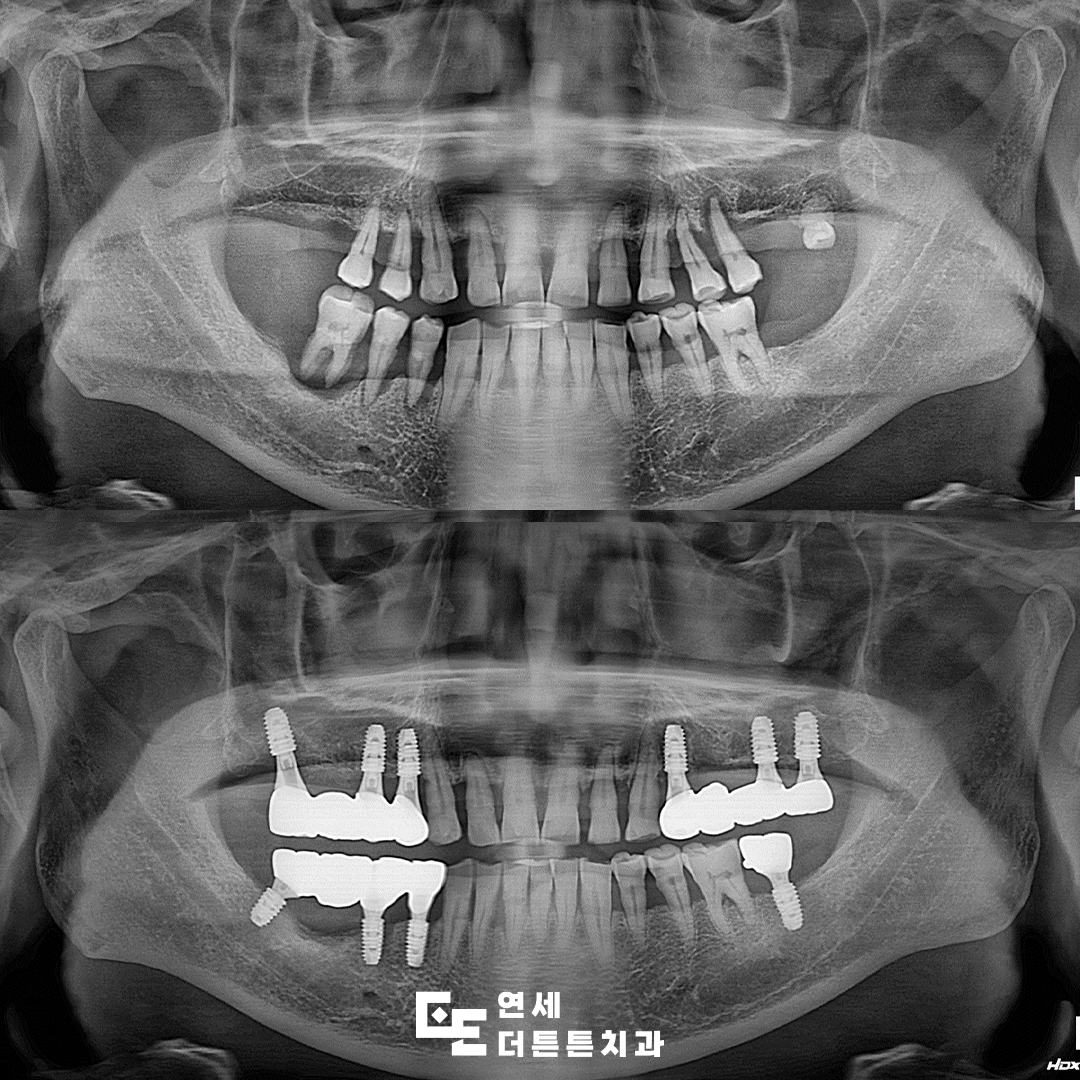

해당 환자분께서는 치아들이 전반적으로 흔들리고 상태가 좋지 않아 식사를 제대로 하기 어렵다며 본원에 내원해 주셨습니다. 기본적인 검진과 함께 파노라마 촬영을 진행한 결과, 심한 치주염으로 인해 잇몸뼈가 많이 소실되어 치아가 떠 있는 것처럼 보이는 소견이 확인되었습니다. 자연치를 유지하기에는 예후가 좋지 않다고 판단되어 발치를 진행한 뒤, 원활한 식사와 기능 회복을 목표로 어금니 부위 도봉동치과 임플란트 식립을 계획하게 되었습니다.

상태가 좋지 않았던 어금니를 발치한 뒤, 임플란트를 식립하고 최종 보철물까지 완성한 모습입니다.

어금니 부위는 구조적으로 강한 저작력이 가해지기 때문에 임플란트 식립 시 잇몸뼈의 양과 밀도, 보철물의 강도 및 형태를 정밀하게 고려해야 합니다. 단순히 인공치근을 심는 과정만으로 충분하지 않으며 잇몸뼈의 상태가 치료 결과에 큰 영향을 미치게 됩니다. 어금니 상실 상태를 오래 방치할수록 치조골 흡수가 빠르게 진행되기 때문에 골량이 부족한 경우에는 뼈이식이나 상악동 거상술과 같은 추가적인 치료가 필요할 수도 있습니다. 도봉동치과 임플란트 어금니 식립은 치료 후 관리 역시 매우 중요한 부분을 차지합니다. 식립 후 약 3~6개월간의 골유착 기간을 거쳐 최종 보철물이 장착되며, 이후에는 정기적인 검진을 통해 임플란트 주위 치조골 상태와 염증 여부를 꾸준히 확인해야 합니다.